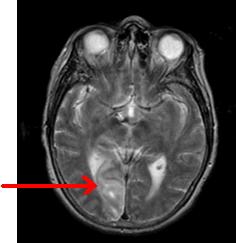

AIRES CEREBRALES ET VISION

img2_cas_clinique.JPG